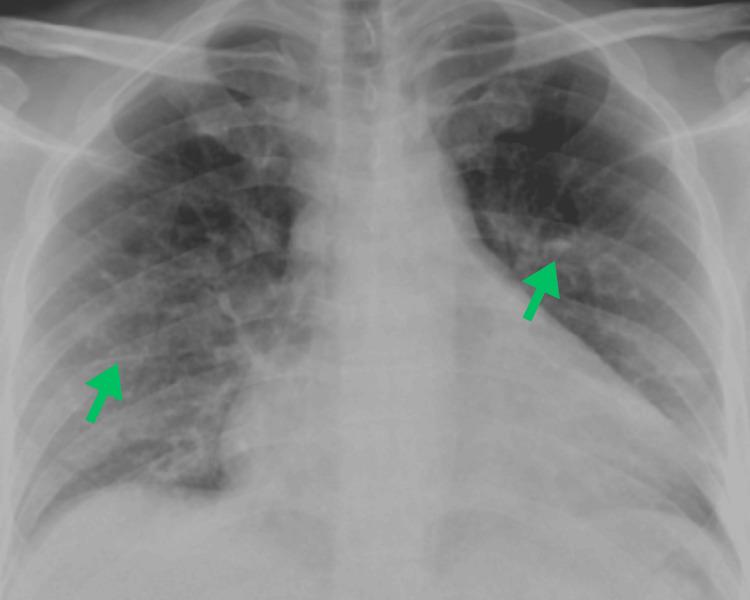

Lung cancer remains the leading cause of cancer-related deaths globally. While smoking-related lung cancers still account for most cases and cause approximately 100,000 deaths annually in the USA, smoking rates have been declining for decades. Lung cancer in never-smokers (LCINS), which tends to affect women and Asian populations, is now the fifth most common cause of cancer-related deaths worldwide. In 2023, over 20,000 lung cancer deaths in the USA were projected to occur in never-smokers, making LCINS the eighth leading cause of cancer-related mortality in the country. As the number of LCINS cases rises, it becomes increasingly important to explore the unique causes and characteristics of the disease, which calls for tailored diagnostic approaches and personalized treatment plans. Lung adenocarcinoma (LUAD) can present with atypical imaging features that often resemble benign conditions, including pneumonia, lung abscesses, post-infectious scarring, atelectasis, mediastinal masses, emphysema, and granulomatous disease. This variability in presentation can hinder accurate diagnosis and potentially delay timely treatment. While lung cancer is uncommon in younger individuals, with only 5.6% of new cases occurring in those under 54 years old, clinicians should maintain a high index of suspicion, as early detection is essential, and atypical cases can be easily missed. Here, we present a complex case involving an unusual radiologic manifestation of a lung mass, in which tuberculosis was initially considered the primary differential diagnosis.

肺癌仍然是全球癌症相关死亡的主要原因。虽然与吸烟相关的肺癌仍然占大多数病例,并且在美国每年导致约10万例死亡,但吸烟率几十年来一直在下降。从不吸烟者中的肺癌(LCINS),往往影响女性和亚洲人群,现在是全球癌症相关死亡的第五大常见原因。2023年,预计美国超过2万例肺癌死亡将发生在从不吸烟者中,使LCINS成为该国癌症相关死亡率的第八大原因。随着LCINS病例数量的增加,探索该疾病的独特病因和特征变得越来越重要,这需要量身定制的诊断方法和个性化的治疗方案。肺腺癌(LUAD)可能表现出非典型的影像学特征,这些特征通常类似于良性疾病,包括肺炎、肺脓肿、感染后瘢痕、肺不张、纵隔肿块、肺气肿和肉芽肿性疾病。这种表现的变异性可能会阻碍准确诊断并可能延迟及时治疗。虽然肺癌在年轻人中并不常见,只有5.6%的新病例发生在54岁以下的人群中,但临床医生应保持高度的怀疑指数,因为早期检测至关重要,非典型病例很容易被漏诊。在此,我们介绍一个复杂病例,涉及肺部肿块的不寻常放射学表现,其中最初将肺结核视为主要鉴别诊断。